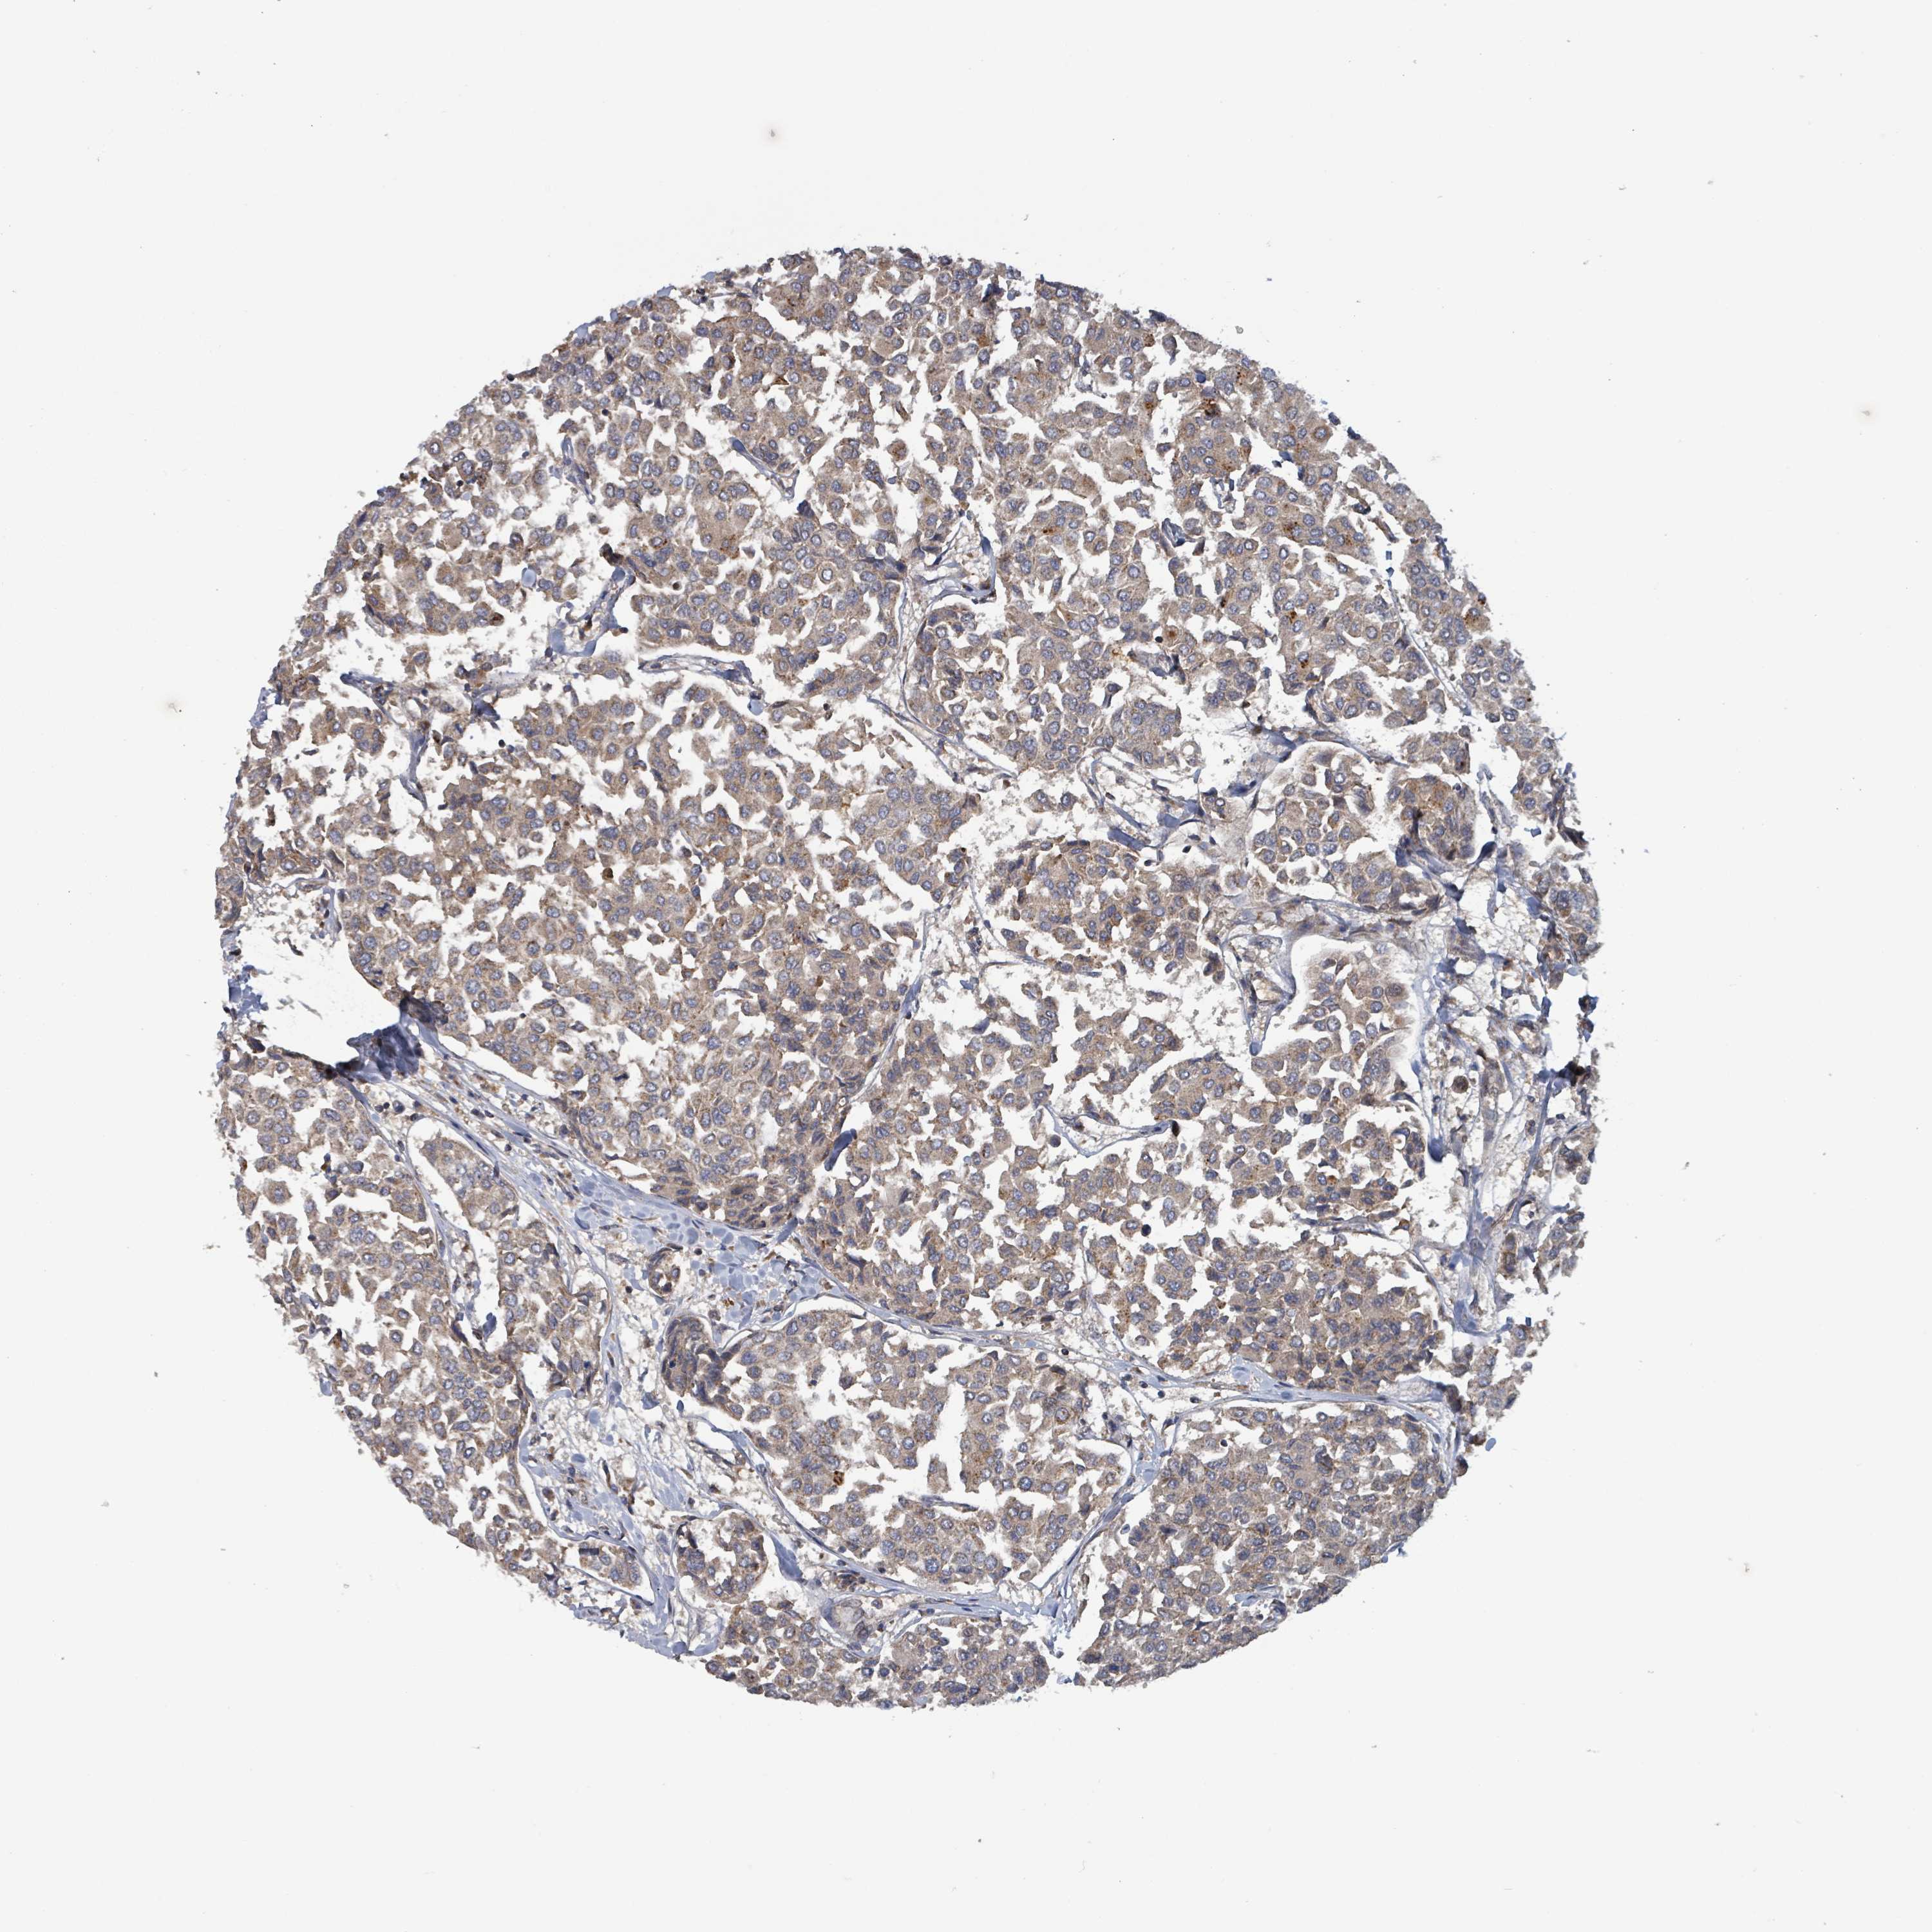

CANCER BREAST CANCER Show tissue menu

BRCA TCGA BRCA VALIDATION PROTEIN EXPRESSION

ANTIBODIES

AND

VALIDATION